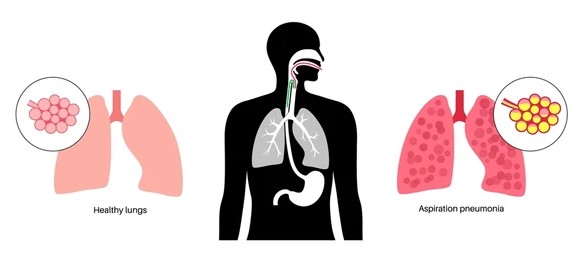

Aspiration Pneumonia is a type of lung infection that occurs when food, liquid, or vomit is inhaled into the lungs. This condition can lead to inflammation, infection, and respiratory problems. Understanding the causes, symptoms, and treatment options for aspiration pneumonia is vital for those at risk of developing it.

Aspiration Pneumonia is a type of pneumonia that results from inhaling foreign substances into the lungs, which can lead to bacterial infection. The condition is often linked to conditions that impair swallowing or the protective reflexes of the airway. Aspiration can occur during eating, drinking, vomiting, or even while lying down, particularly in those with certain medical conditions.

- Chest X-ray: A chest X-ray is often used to identify signs of infection or fluid buildup in the lungs.